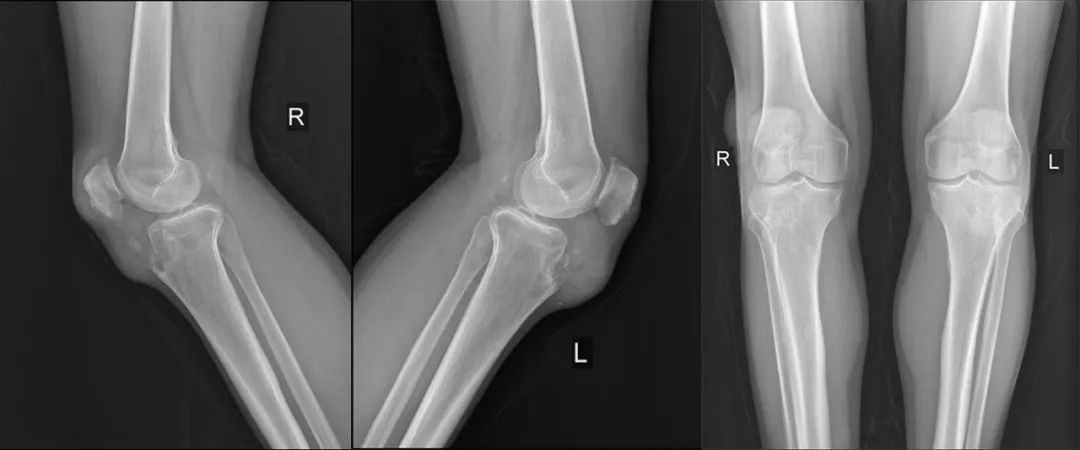

张先生再次入院,初步查体显示:右肘关节后侧、左膝关节髌骨上缘、左膝关节髌骨下缘、右膝关节髌骨上缘双侧、右膝关节髌骨下缘、右外踝、右足背近端等多处包块,左足第四趾末节指腹,性质为痛风石;其余多处关节增粗。

(术前)